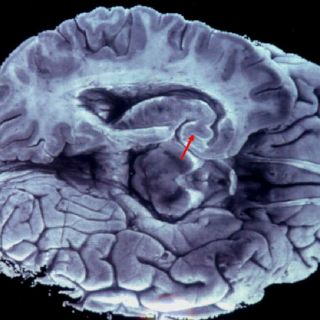

WASHINGTON, ESTADOS UNIDOS (19/MAR/Y2013).- Las mutaciones identificadas recientemente en un gen que hace que las células sean inmortales desempeñan un papel crucial en tres de los tipos de cáncer de cerebro más comunes, según un artículo que publica hoy Proceedings of the National Academy of Sciences.

Estos tipos de cáncer incluyen melanomas, liposarcomas, carcinomas hepatocelulares, carcinomas de célula transicional en las vías urinarias, carcinoma espinocelular de la lengua, blastomas medulares y subtipos de gliomas, incluido el 83% de los glioblastomas primarios, el tumor cerebral mas común en los adultos y con una supervivencia promedio de solo 15 meses.